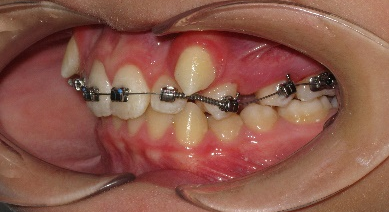

В полости рта: смыкание первых моляров по дистальному типу. Сужение зубных рядов в боковых отделах. 13 и 23 - вестибулярное и супраположение с дефицитом места в зубном ряду на величину ширины коронки клыка. Глубокая резцовая окклюзия.(рис.2.)

Рис.2.Смыкание зубных рядов пациента А. до лечения и окклюзионный вид.